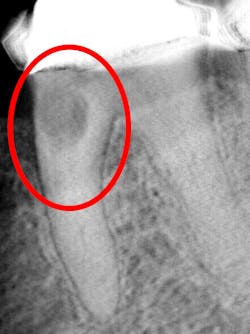

I see more complications and pathologies when using 3D tomosynthesis than I ever did with my old 2D images (figure 4). I can treat more because I can see more bone loss, interproximal caries, fractures, resorptions, abscesses, and more (figure 5).

In fact, twice today I was able to see something with Portray that wasn’t visible in the original 2D x-ray (figure 6). I don’t always take 2D images now, but I do when I think the case is straightforward or the patient has very little dental history. I often end up taking a tomosynthesis image just to be safe. With the 3D image I can scroll from buccal to lingual through the tooth and get much more data (figure 7). The new system has replaced my 2D PAs and bitewings.

Fortunately, 3D intraoral tomosynthesis found its way into the dental field. Based on the findings from a study out of the University of North Carolina, dentists who use 3D tomosynthesis for intraoral x-rays can detect approximately 36% more caries (figures 8 and 9).1 That’s tremendous!